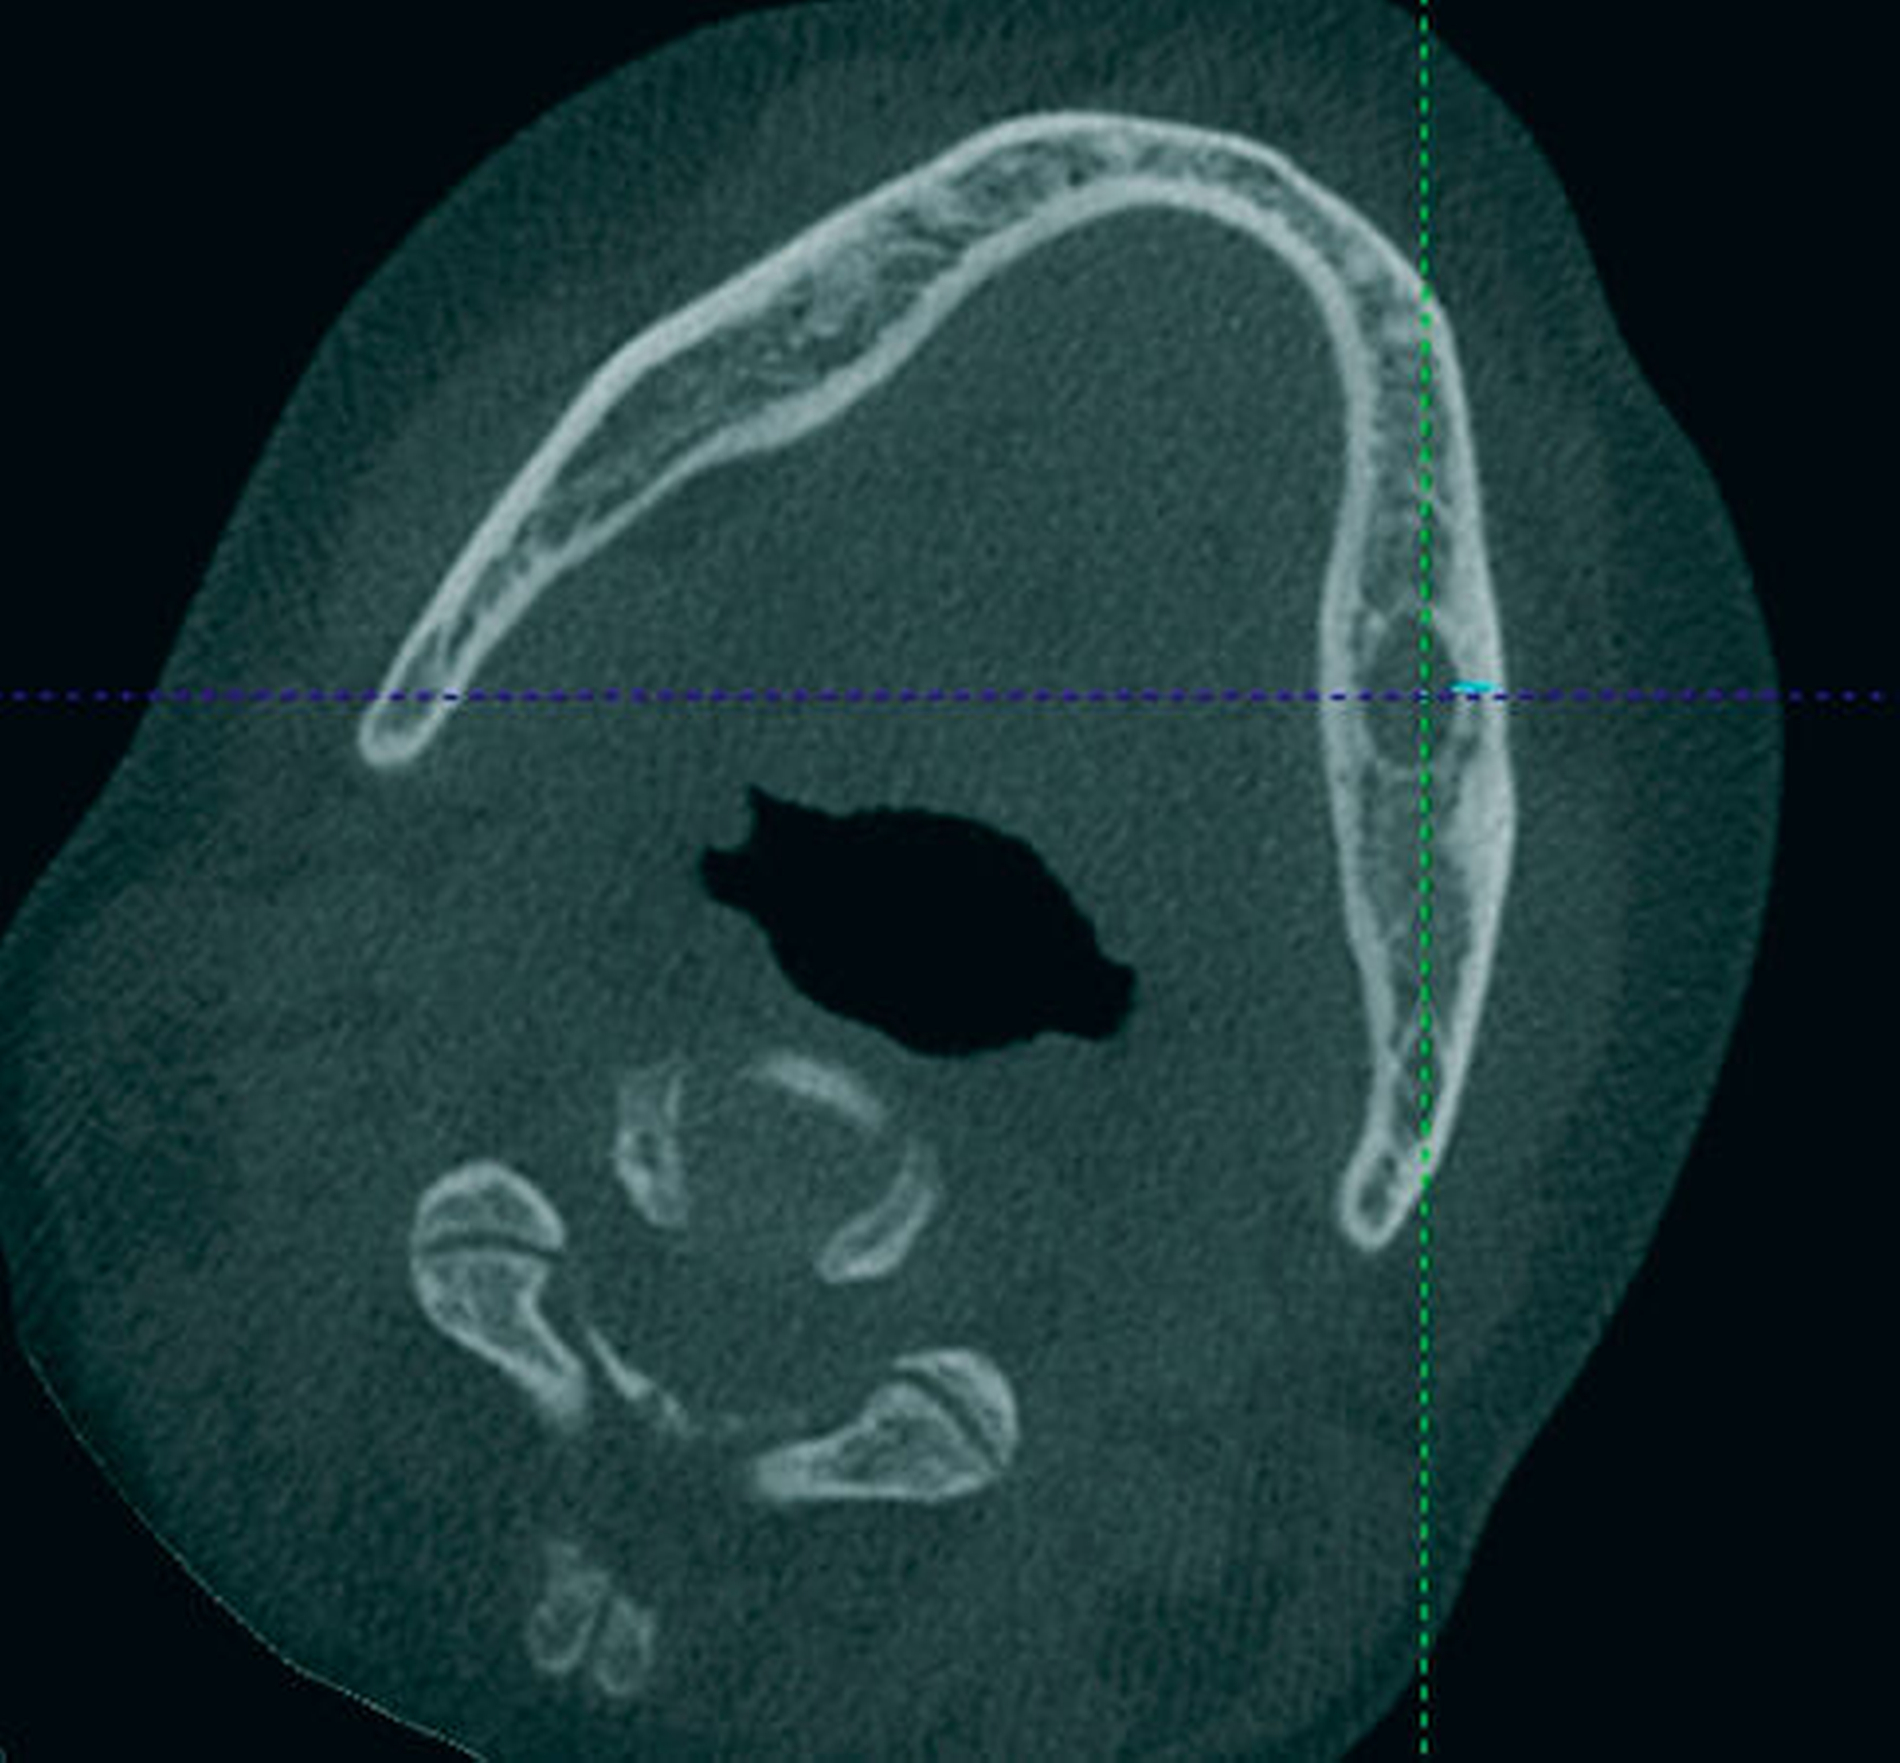

Bis 2017 hatten sich keine Auffälligkeiten gezeigt. Nun stellte sich in der Kontrolle mittels Panoramaschichtaufnahme radiologisch der Verdacht auf ein Rezidiv. Im Bereich des Corpus-Kieferwinkel-Übergangs zeigte sich eine blasig anmutende Transluzenz knapp oberhalb der Projektion des N. alveolaris inferior. Sensibilitätsausfälle lagen nicht vor. Die erweiterte Bildgebung mittels digitaler Volumentomografie bestätigte eine Lage direkt cranial des Nervens mit einem Durchmesser von 0,7 cm x 0,5 cm x 0,5 cm (Abbildung 2).

Aufgrund der tiefen intraossären Lage ohne direkten Zahnbezug oder andere klare Orientierungspunkte wurde zur gezielten Ansteuerung auf Basis des DVT-Datensatzes eine Osteotomie-Schablone 3-D-gedruckt (Material: MED 610, Drucker: EDEN 260V, Stratasys), die den Osteotomiezugang genau verschlüsselte (Abbildung 3a). Intraoperativ konnte dadurch die Keratozyste gezielt entfernt werden, ohne dass eine großflächige Osteotomie notwendig war oder ein erhöhtes Risiko für die Verletzung des N. alveolaris inferior bestand (Abbildung 3b). Der Befund wurde zystekotomiert und die Knochenhöhle zusätzlich ausgefräst (Abbildung 4). Auch die postoperative radiologische Kontrolle bestätigte eine optimale Lage der Osteotomie (Abbildung 5). Die postoperative Heilung war unproblematisch, drei Jahre nach dem Eingriff ist die Patientin rezidivfrei (Abbildung 6).